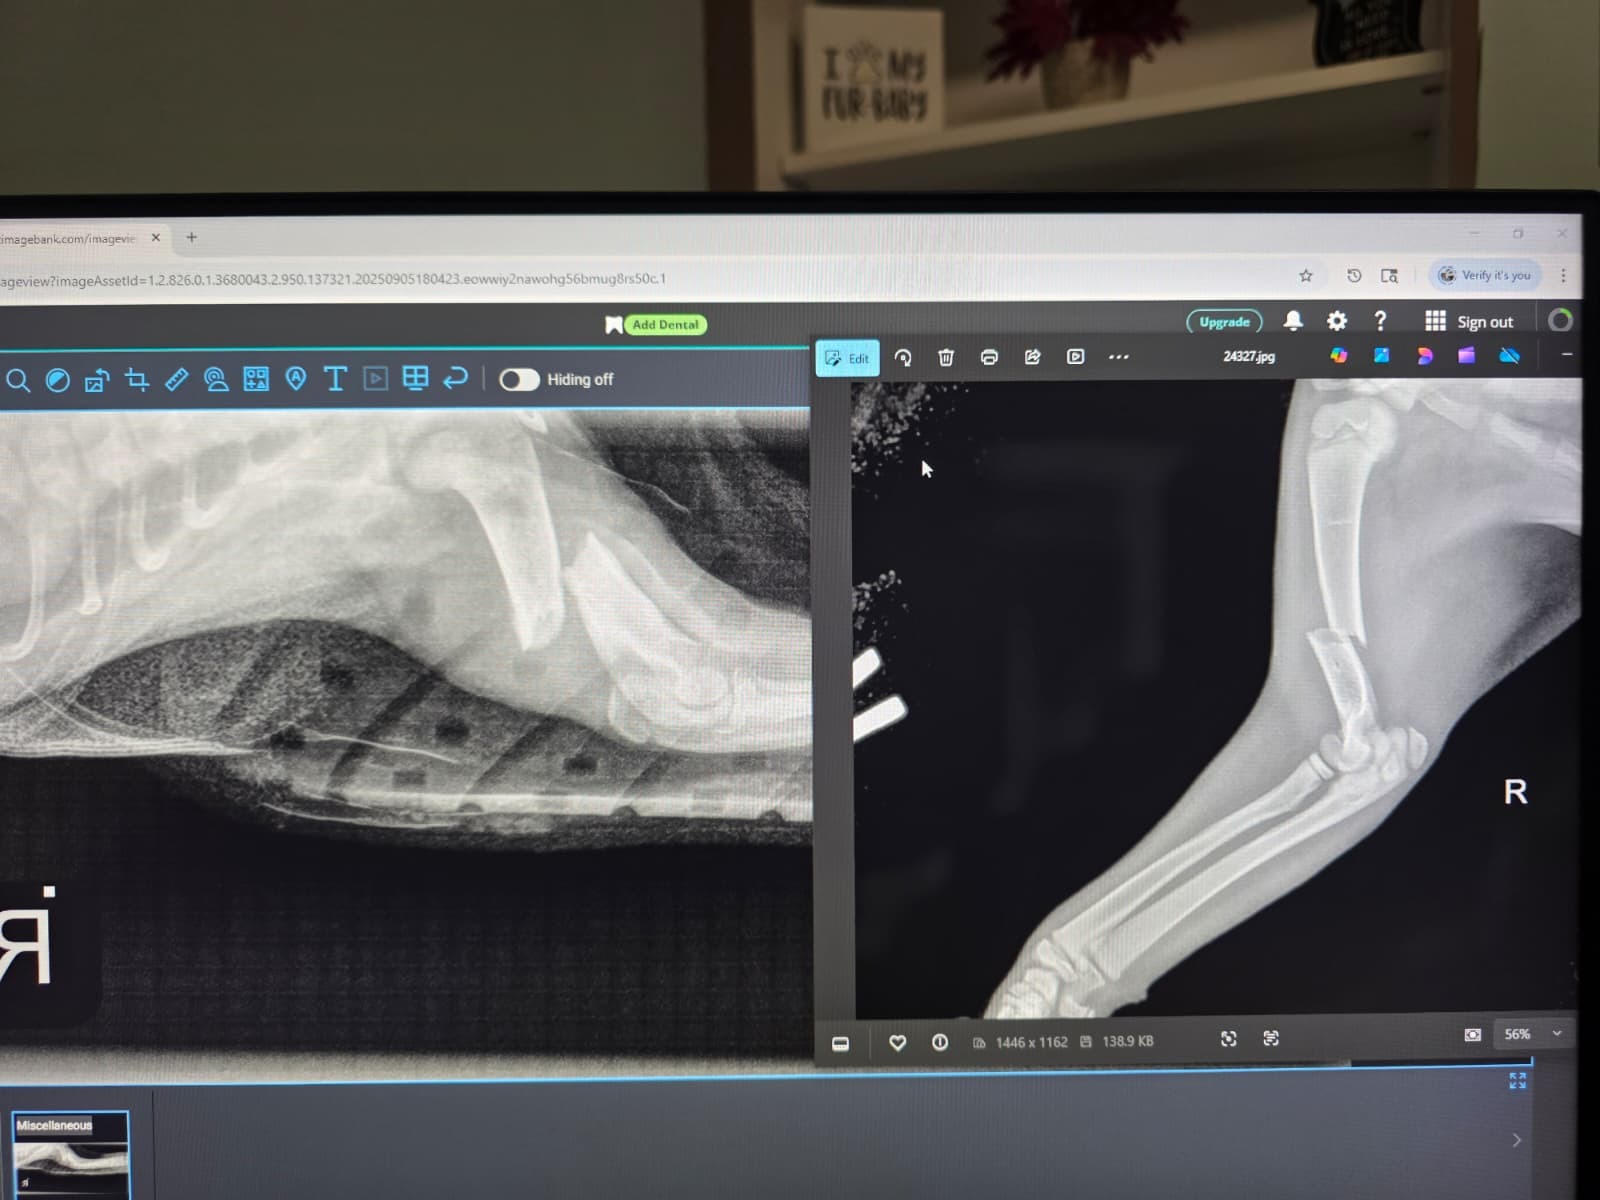

This is our adorable little orange kitten named Colby Jack, or as we call him: CJ. He is mischievous and curious but incredibly sweet and affectionate. On 08/24/25, he knocked over a very heavy object that landed on his arm. On 08/25/25, we took him in for an x-ray, which confirmed that his arm had been broken. We splinted his arm since the quote for surgery was well out of our budget. We opted to try just splinting his arm to see if we could line it up to naturally heal. He seemed to be in less pain and back to his normal self, until 09/05/25 when we took him in to change his splint. We got follow up x rays on this visit which showed that the fracture is only getting worse. As shown in the attached x ray, the two separated ends of the broken bone are now overlapping each other, being pulled apart by the attached ligaments (original x ray is to the right and the most recent to the left). In short, it will not be possible to just merely splint the arm. The vet gave us 3 options: surgery, amputation, or to put him down. The third is simply not an option for us, but the vet only gave a window of about a week or 2 until we have to make a decision. We really need help to get surgery or amputation. We are looking into a variety of options under these two options. However, we need financial help as have tried everything to finance such an expense. We tried applying for Care Credit, and neither of us was approved. Our income is considered too high to qualify for financial support from all the non profits we looked into. We certainly did not want to have to be put in this situation but we simply have no other choice but to desperately ask for help.